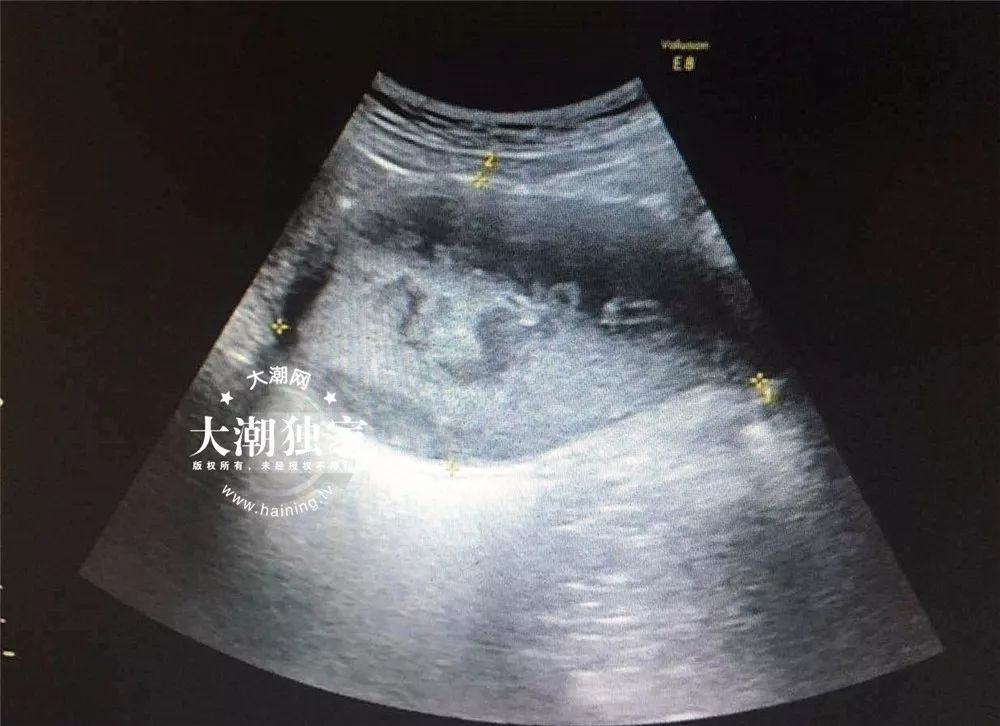

图:这是阴道b超显示的图像,卵巢在上面根本看不见